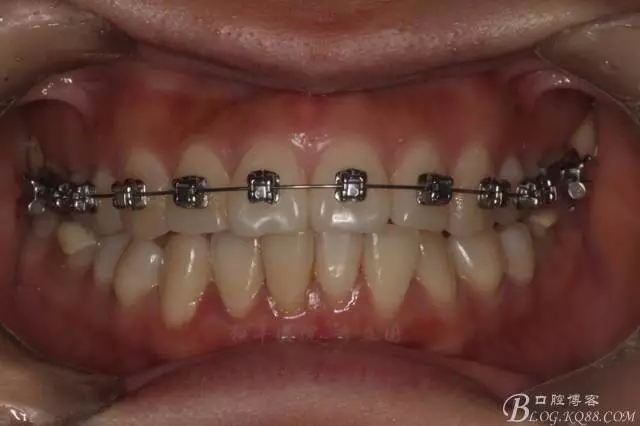

該病例主要為17、27頰側(cè)位同時伴有伸長,當然種植支抗可以解決,但還有簡單實用的辦法嗎?如圖,在橫腭桿遠中延伸出牽引鉤,位置盡量遠離合平面,7粘舌側(cè)扣,牽引力的方向為壓低及舌向,下圖為兩個月的效果,17已到位,27還未到位。